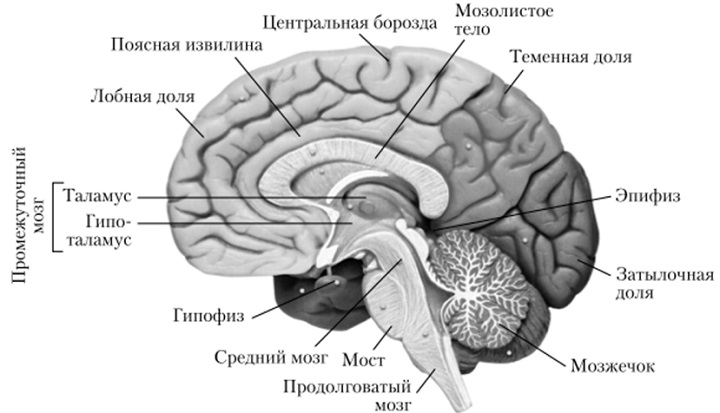

Анатомические снимки верхнелатеральной поверхности головного мозга